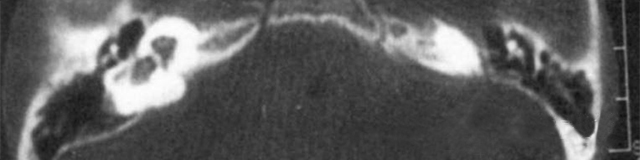

主要依靠顳骨高分辨CT和內耳MRI。

雙側內耳畸形:左側無內耳迷路及內耳道機構,為米歇爾畸形;右側空耳蝸及前庭擴大,為先天性耳蝸畸形